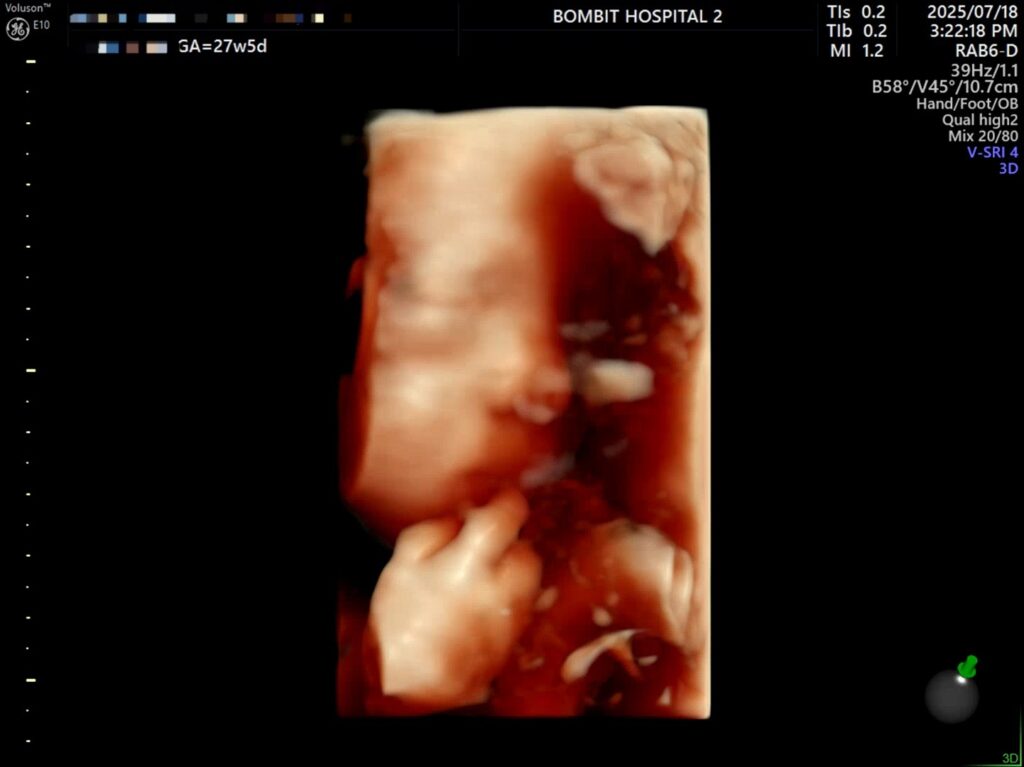

– 통통한 손가락

입초로 본 단비 얼굴은 정말 너무너무 귀여웠다!! 보면서 코가 복코같이 눌려있다고 생각했는데,, 선생님은 아기 콧대가 높다고 했다. 엄마를 닮아서 그런 듯(?)ㅋㅋㅋ